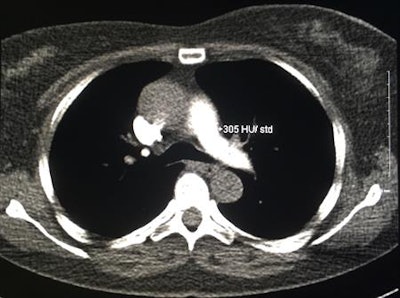

Patient dose can be reduced in several ways, but they are directed at the diagnostic component of the CTPA study. A typical CTPA study comprises three components: a patient topogram, a contrast-monitoring scan, and a diagnostic scan. The role of the contrast-monitoring scan is to determine the optimum timing between the injection of contrast material and CT data acquisition to obtain adequate pulmonary arterial contrast enhancement, the researchers noted.

"In practice, the contrast-monitoring component entails the continuous imaging of the pulmonary trunk after contrast injection has begun, which can either trigger the diagnostic scan at a predetermined Hounsfield level (i.e., bolus tracking) or can be used to accurately time a separate diagnostic study (i.e., test-bolus timing)," they wrote.

Contrast-monitoring techniques contribute little to the total DLP, but due to the short scan length, the technique does require repetitive scanning through breast tissue when monitoring the pulmonary trunk.